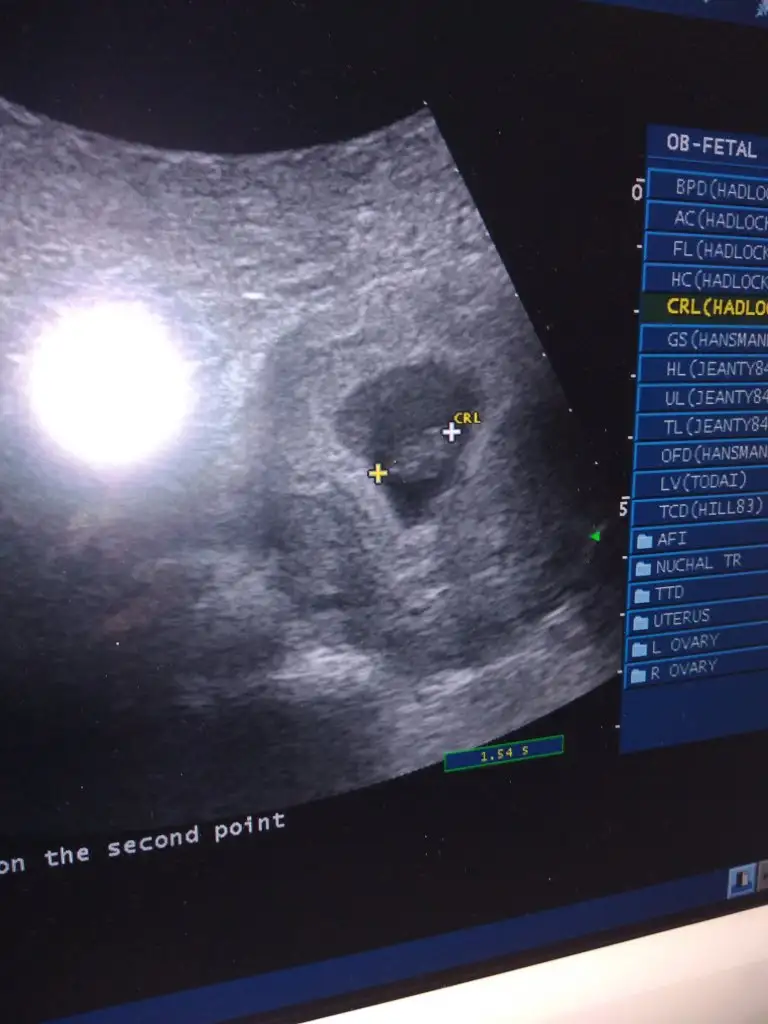

Ben hic anlamam cnm ama rabbim saglikla kucagina almayı nasip etsin insCinsiyet tahminleriniz varsa alabiliriz meraklı biriyimdir![]()

Erlek diyorm benCinsiyet tahminleriniz varsa alabiliriz meraklı biriyimdir![]()

Bende anlamıyorum pek hadi hayırlısı Rabbim sağlıkla kucağınıza aldırsin insAllahCinsiyet tahminleriniz varsa alabiliriz meraklı biriyimdir![]()